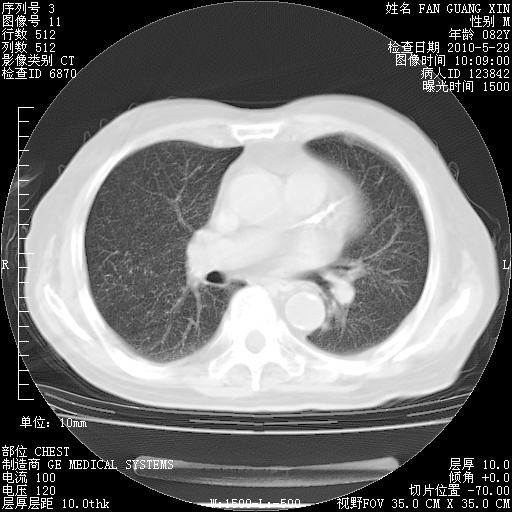

再治疗10天后的肺部CT

再治疗10天后的肺部CT 纵膈窗

阅读此次胸部CT,肺间质渗出性改变较入院时有吸收。目前从体温、白细胞、中性分叶明显增高,肯定存在细菌感染(发生医院感染哦,若无消化道及泌尿系统等感染的依据,肺部感染可能大)。若你院头孢哌酮舒巴坦钠耐药率较高,同意你的方案,若48小时体温仍高,可考虑使用碳青霉稀类抗菌药物,同时可予超声雾化、注意滴数时加大液体量。白蛋白33.30g/L较低哦,需加强营养等支持治疗。